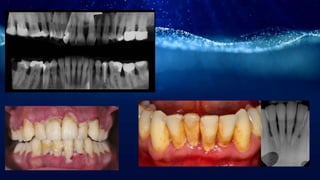

Chronic periodontitis

• It is inflammatory disease of supporting tissues

of teeth caused by specific micro-organism

resulting in progressive destruction of

periodontal ligament and alveolar bone with

pocket formation,recession or both.

• Chronic periodontitis,formerly known as adult

periodontitis or chronic adult periodontitis is the

most prevalent form of periodontitis.

• Most commonly seen in adults.

• Age associated but not age related.

• Chronic periodontitis is considered a site-specific

disease.

Clinical features

• Supra and subgingival plaque accumulation

• Gingival inflammation

• Pocket formation

• Loss of periodontal attachment

• Occasional suppuration

• Poor oral hygience-gingiva is typically may be slightly to moderately

swollen

• Color-pale red

• Consistency-soft or firm

• Surface topography-loss of stippling

• Flattened or cratered papillae

• Furcation

• Tooth mobility

• BOP